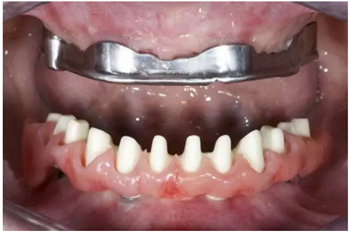

試戴上頜NobelProcera CAD/CAM海德式桿卡(IBO)以及下頜NobelProcera二氧化鋯種植橋(PIB)。

手術(shù)后16周最終修復(fù):上頜覆蓋義齒是卡扣在鈦桿卡(IBO)上,義齒牙冠部分是由二矽酸鋰玻璃陶瓷制作的單冠。下頜的氧化鋯種植長橋(PIB)上同樣也制作二矽酸鋰玻璃陶瓷的單冠并進(jìn)行粘接。